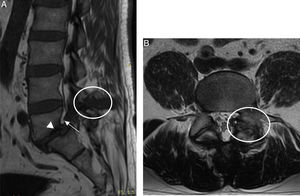

Caso clínicoVarón de 44 años, acudió al hospital por lumbalgia. Un año antes inició con lumbalgia progresiva e irradiación a miembro pélvico izquierdo. Seis meses antes presentó artritis de rodilla izquierda de inicio súbito, remitiendo con antiinflamatorios. El paciente se hospitalizó, su examen físico mostró marcha independiente, antiálgica, claudicación, disminución de la movilidad de columna por dolor, Lasegue y Bragard positivos, hipoestesia en dermatoma L5-S1 y RI con derrame articular. La biometría hemática, urianálisis, velocidad de sedimentación globular y proteína C reactiva con parámetros normales, ácido úrico sérico de 11,8mg/dl y ácido úrico en orina de 24h: 560mg. La radiografía con espondilolistesis lítica de L5, en la resonancia magnética (RM) señal hipointensa en T1 y heterogénea en T2 localizada en el espacio interespinoso de L4-L5, y en articulación facetaria izquierda que invade el neuroforamen izquierdo con lisis bilateral de la pars interarticular (fig. 1). El ultrasonido de rodilla izquierda mostró doble contorno del cartílago del cóndilo femoral medial (fig. 2A) y quiste de Baker de paredes gruesas con puntilleo hiperecoico en su interior (fig. 2B). Se efectuó laminectomía, liberación radicular de L5, fijación transpedicular L5-S1 y artrodesis postero-lateral. El estudio histopatológico del material removido por cirugía reportó material amorfo anfófilo acelular constituido por histiocitos epitelioides que fusionan sus citoplasmas formando células gigantes multinucleadas de tipo a cuerpo extraño (fig. 2C).

RM columna lumbosacra. A) Plano sagital en T1 con imagen hipointensa en espacio interespinoso L4-L5 (círculo) que invade el neuroforamen (flecha) y espondilolistesis de L5 (cabeza de flecha). B) Plano axial en T2 con imagen heterogénea en articulación facetaria izquierda con lisis bilateral de la pars interarticular (círculo).